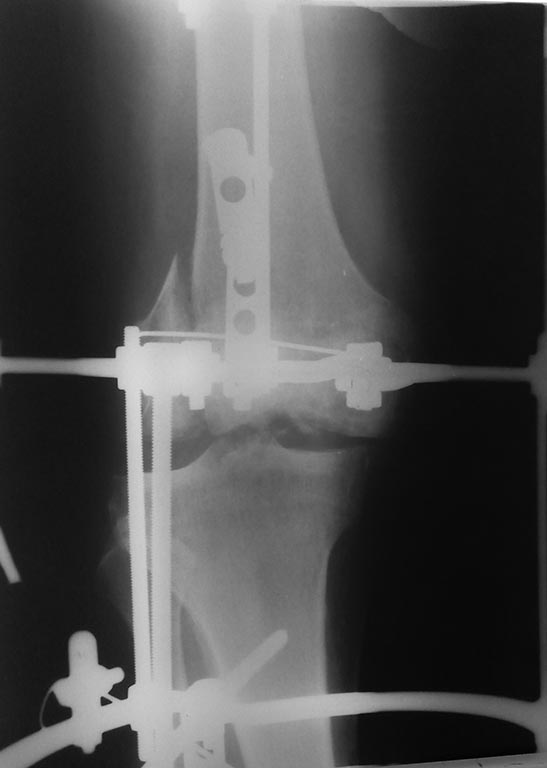

пациент 57 лет. травма в октябре 2016г. ДЗ: Открытый вывих правой голени с переломом наружного мыщелка бедренной кости. при поступлении произведено ПХО раны, открытое вправление, наложение аппарата внешней фиксации. в настоящее время раны зажили без воспалительных явлений.имеется смещение отломка наружного мыщелка. нужна помощь в определении тактики дальнейшего лечения.

Мыщелок это полбеды,что со связочным аппаратом?!!!.. ну и до уровня Кашпировского наш форум ещё далёк,чтоб по одному снимку на ноги ставить больных.

Уважаемый коллега, информации и в самом деле мало. Желательно, конечно, увидеть внешний вид конечности и R-граммы в двух проекциях до и после операции. Тут наверняка имеются серьезные повреждения связочного аппарата. Для уточнения можно снять аппарат, наложить гипс и сделать МРТ. А если повреждение костных структур выражается только тем, что мы видим на этом единственном снимке, то оптимальным вариантом кажется синтез наружного мыщелка опорной пластиной. Эндопротезирование здесь может подождать. И при остеосинтезе иметь в виду, что наверняка придется делать пластику крестообразных связок.

Полный диагноз:тяжелая сочетанная травма.ЗЧМТ.Ушиб головного мозга. ушибленная рана теменной области слева. контузия обоих глаз. закрытая травма грудной клетки. перелом 2-5 ребер справа, 3 ребра слева. закрытый оскольчатый , фрагментарный перелом левого бедра( перелом шейки, оскольчатый перелом на протяжении всей диафизарной части).открытый вывих правой голени с переломом наружного мыщелка бедренной кости.разрыв ПКС,ЗКС. травматический шок 2 ст.

при поступлении произведено ПХО раны, открытое вправление, наложение аппарата внешней фиксации.гипсовая иммобилизация левой нижней конечности. интенсивная терапия в ОРИТ 6 суток. на 11 сутки после травмы произведена операция - остеосинтез левой бедренной кости. послеоперационная рана зажила первичным натяжением. имело место умеренное воспаление вокруг раны в области правого коленного сустава, в связи с чем было решено воздержаться от погружного остеосинтеза наружного мыщелка бедра. на 22 сутки после травмы больной выписан на амбулаторное лечение. вопрос о восстановлении связочного аппарата не обсуждался в связи с открытым характером перелома. настоящая госпитализация плановая, для остеосинтеза наружного мыщелка бедренной кости. возник вопрос о целесообразности восстановления крестообразных связок с оглядкой на возможно предстоящее эндопротезирование коленного сустава.

Если был вывих голени, то нет сомнений в том, что обе крестообразные связки повреждены, и не только. Тем более на снимке видно поврежденное межмыщелковое возвышение. И т.к. они являются основными статическими стабилизаторами коленного сустава, наряду с коллатеральными связками необходимо их конечно восстановить. Но начинать, как мне видится, нужно все-таки с мыщелка. Опять же если произошел перелом наружного мыщелка, значит наружная коллатеральная связка цела, и его восстановление приведет к стабилизации сустава Согласен с коллегой, что можно перевести АВФ в гипс и сделать МРТ, но можно все это посмотреть и глазом через артроскоп, что более информативно. Это если опираться на представленную информацию. А вообще, конечно, хотелось бы знать характер травмы, не было ли ангионеврологических нарушений, что из себя представляет пациент, были ли проблемы с суставом до травмы и т.д. В порядке ли анализы?

В момент ПХО было бы идеальным сделать и фиксацию мыщелка винтом (или двумя, по ситуации). Это значительно стабилизировало бы сустав, держать в АНФ понадобилось бы в течение меньшего времени. Был аналогичный случай в результате железнодорожной травмы. В момент вторичной хирургической обработки выявил, что на наружном мыщелке висит большой мыщечный лоскут.. При репозции и фиксации сустав очень здорово укрылся мягкими тканями, заживление пошло лучше. А сейчас.. Думаю, начать с КТ коленного сустава, определиться как и чем фиксировать мыщелок. Очевидно, что была серьезная травма связок. При репонированном изначально мыщелке можно было бы после снятия АНФ думать о восстановлении связок. А теперь... Зафиксировать мыщелок, дождаться его сращения. Возможно, одним этапом сделать санационную артроскопию. Далее готовиться к эндопротезированию. После удаления пластины, например

Вспомнился недавний позиционный винт...Все прицепились к мыщелку.Та этот мыщелок уже прирос ниплохо и не требует никакой иммобилизации и первостепенной коррекции и как его фиксировать всем известно(либо опорная пластина,либо винты),а вот подвывих голени вызывает больше тревоги!По-моему стоит начать с пластики связок и пока связки "прирастут",мыщелок конкретно прирастет и нога будет опорной.А так ща фиксируем мыщелок и будем ждать пока прирастет, а потом ждать когда связки станут состоятельны...ну или подождать ещё месяц(всеравно праздники на носу)и потом оценить функцию сустава(может связки оторвались от места прикрепления вместе с межмвщелковыми возвышениями и прирастут к тому времени,хотя в диагнозе они не звучат).